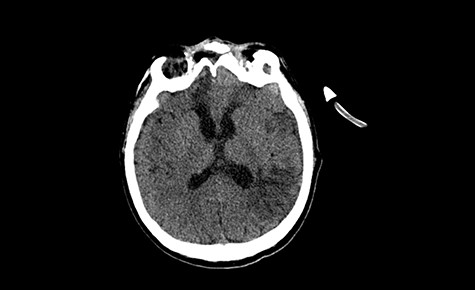

A 49-year-old patient presented after surgical treatment of nasal polyps, with headache and consciousness disorders (behavioral changes, drowsiness and allophenic orientation disorders). Computed tomography (CT) scan showed (Fig. 1) a presence of blood in fluid spaces, widening of the ventricular system (without active hydrocephalus features) and presence of air in the frontal horns of the lateral ventricles and features of cerebral edema. Due to the subarachnoid hemorrhage, an angio-CT and CT scan was performed, showing no vascular malformation. The patient's condition deteriorated with a drop in Glasgow Coma Scale (GCS) to 9, strongly expressed meningeal syndrome and a fever of > 38°C. In the performed cerebrospinal fluid examination a typical picture for bacterial infection, cultures negative. Treatment was implemented in accordance with the neuro-infections algorithm. Clinical and laboratory features of neuroinfections have withdrawn. The neurological condition of the patient improved to GCS 11. Control head CT (Fig. 2) showed enlargement of the ventricular system with cerebrospinal fluid transudation.

Head CT after polypectomy—presence of blood in fluid spaces, widening of the ventricular system, presence of air in the frontal horns of the lateral ventricles, features of cerebral edema. (Department of Neurosurgery Neurotraumatology and Pediatric Surgery own material).

In described case, a head CT scan after polypectomy confirmed the subarachnoid hemorrhage (Fig. 1). In addition, the presence of air in the ventricular system was visible, and presence of defects of the upper left orbital wall and ethmoid on both sides (Fig. 3). In the CT scan sphenoid sinus, frontal and ethmoidal sinuses on both sides and right maxillary sinus airless, filled with blood and soft tissue. The changes also concerned the lateral part of the left maxillary sinus (Fig. 4).